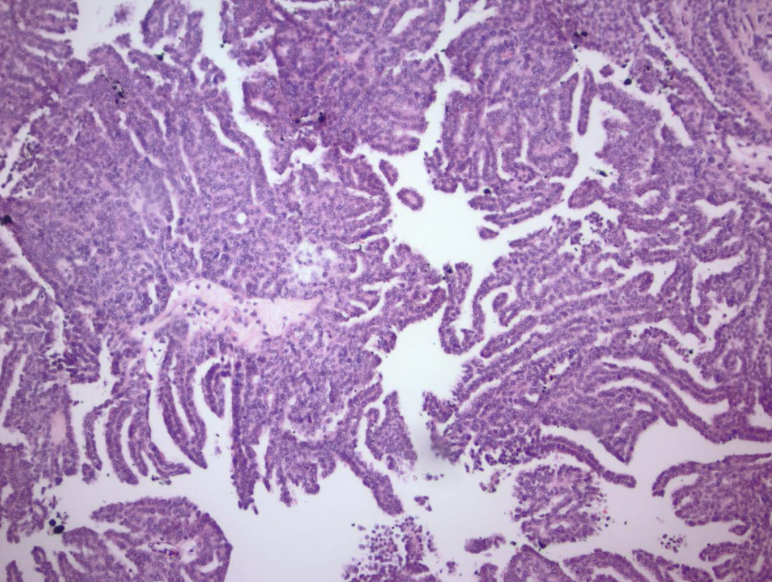

papillary RCC

arise from distal convoluted tubules

multifocal and bilateral

MET

papillary RCC

papillary vs. clear cell: arise in distal tubular epithelium

papillary RCC

papillary RCC